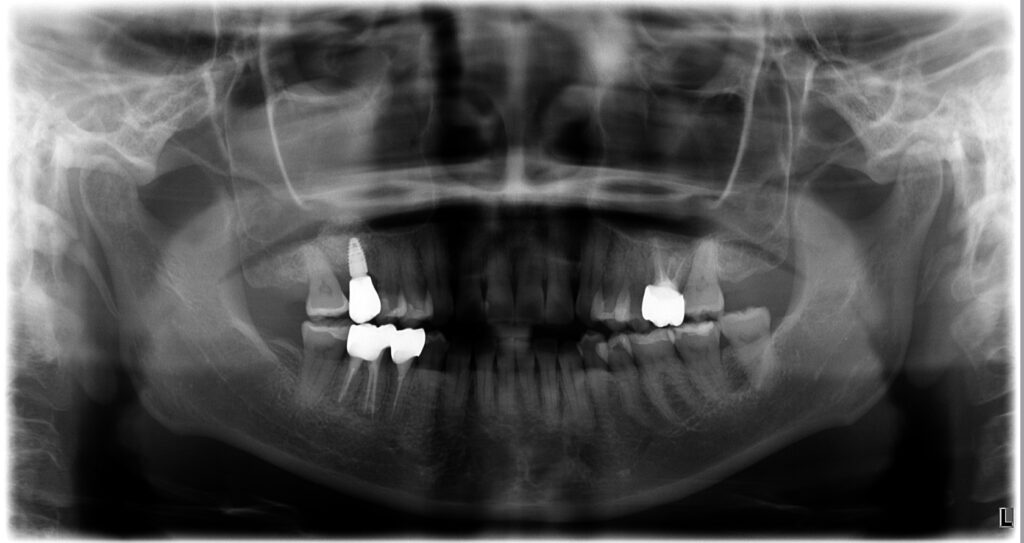

治療後の状態

治療後には、以下のような改善が見られました。

・ 痛み・腫れの消失

・ レントゲンで透過像が縮小し骨の回復

・ 歯肉が自然で健康的なラインに

・ セラミッククラウンが自然に適合

・ 咬合が安定し噛みやすくなる

外科なしでここまで改善できるのは、

根管治療・補綴・咬合の3つを総合的に設計しているからこそ です。